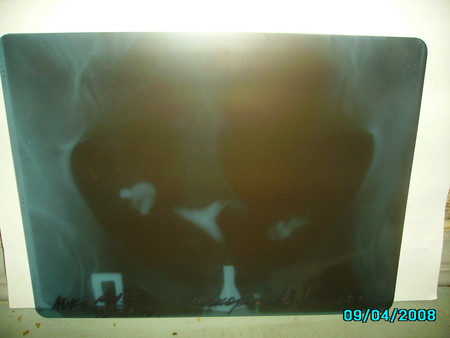

Ситуация такая - было 2 внематочные, после первой я прошла курс реабилитации, были и физиотрерапия, и гирудотерапия, лангидаза, капельницы. В результате - 2 я внематочная. Оба раза мне делали лапару, врачи говорили, что трубу очень плохие. И вот я решилась на ГСГ - было совсем не больно, но результат польностью непроходимые трубы. Сейчас решается вопрос об удалении труб, потом ЭКО. Я согласна на удаление, т.к. лечить их я уже устала, да и все врачи говорят - это бесполезно. Мне, конечно, очень страшно, но я буду делать все, что говорят доктора.

Врач, глядя на снимки сказала только, что трубы непроходимы. А я в этом ничегошеньки не понимаю. Посмотрите вы.

как удалять трубы!!!! у тебя на снимках видно. как контрастное вещество излилось в брюшную полость, у меня точно такой же снимок, даже намного хуже видно излитие вещества

Есть, сактосальпинкс в левой трубе, а в правой обе беременности были, ее тоже нет смысла сохранять

а у тебя по сторонам матки светлые пятна - разве это не признак прохождения контраста?

А я понятия не имею. Сказали - непроходимы, и на этом всё.